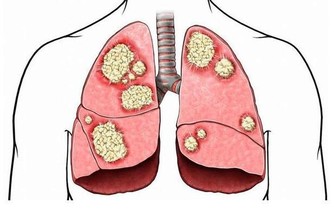

研究認為,苯是染髮劑中最基本的化學物質,對造血系統具有強烈毒性。染髮劑使用一個階段后,苯會沿頭髮浸入頭皮毛細血管,破壞造血系統,引起頭暈、乏力、皮下、內臟和腦出血,更加嚴重的是誘發癌症。近年來,醫學界常使用「染髮白血病」這個名詞,表明了染髮與白血病的關係。

美國和加拿大一項研究調查了766名成人白血病患者和623名沒有得過白血病的健康人,與沒有使用染髮劑的人比較,使用持久性染髮劑和半持久性染髮劑者患急性白血病的危險性較高。